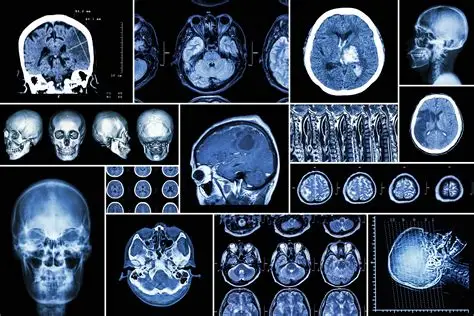

Medical Imaging Technology